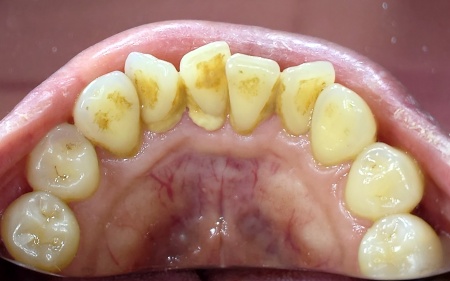

30代女性 重度の歯周病に対して歯周内科治療を行った症例

- 歯石除去

- 歯周病

- 治療期間の目安 -

-

治療回数の目安

2回

※保険診療回数・ブリッジ治療は含まれない -

治療費総額の目安

55,000円(歯周内科治療)

※保険治療費・ブリッジ治療費は含まれない